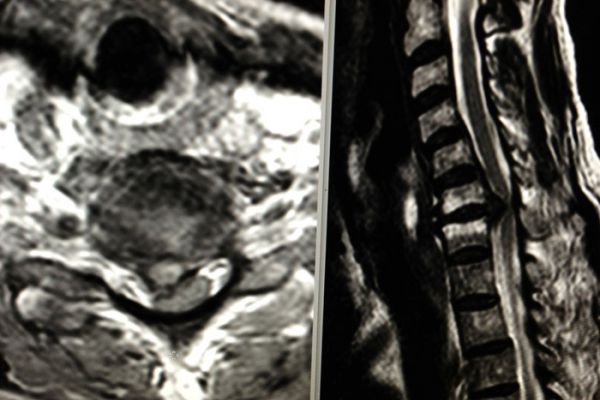

Die Magnetresonanztomographie nutzt keine Röntgenstrahlen sondern Magnetfelder und hochfrequente elektromagnetische Wellen. Das durch hochempfindliche Antennen gewonnene Signal wird in einem komplizierten Auslese- und Messverfahren umgesetzt und in ein Bild umgewandelt.

Der Vorteil der MRT ist die oft bessere Darstellbarkeit entzündlicher und tumoröser Veränderungen in sämtlichen Weichteil-Geweben, bzw. -Strukturen; Nerven- und Hirngewebe werden z.T. erst durch die MRT-Untersuchung hinreichend beurteilbar. Oft wird Kontrastmittel zusätzlich benötigt, um Entzündungsherde oder auch Tumorgewebe noch besser darzustellen.

• Gehirn und Nervenstrukturen